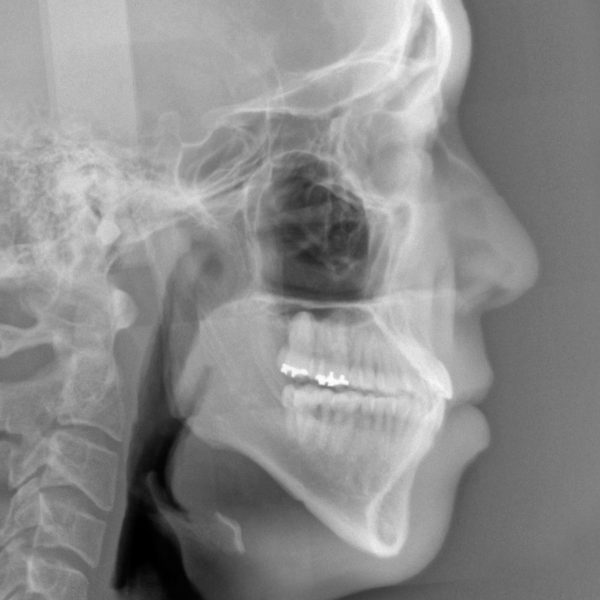

19歳 女性「手術をしないで 受け口を治したい」( 骨格的な反対咬合 )

19歳の女性です。 「受け口を治したい」との事で来院されました。

お口の中を診てみますと。。。 前歯は反対咬合そして右も左も全ての歯が逆被蓋

う~ん・・・ 重度の反対咬合です。

骨格的な要因を有する反対咬合です

受け口の程度は非常に強く、骨の非対称、顎の偏位がある症例です

下顎の骨の長さもずいぶんと長いです

本当は 顎の骨を切る手術を伴う矯正治療が必要な症例です。

治療後のレントゲン写真です